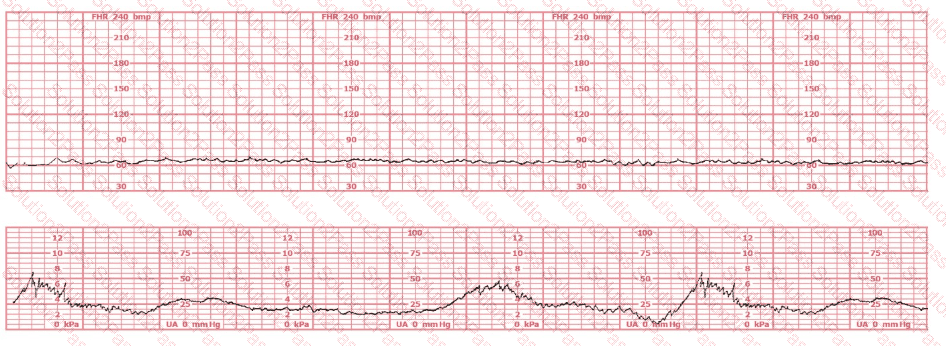

The tracing shown is from a woman at 28-weeks gestation in the post-anesthesia care unit (PACU) after an appendectomy. She is alert and awake. Based on this fetal heart rate pattern, the most appropriate intervention is:

The fetal heart rate tracing shown demonstrates:

The tracing shown is a:

The most probable underlying fetal physiologic cause for this tracing would be: